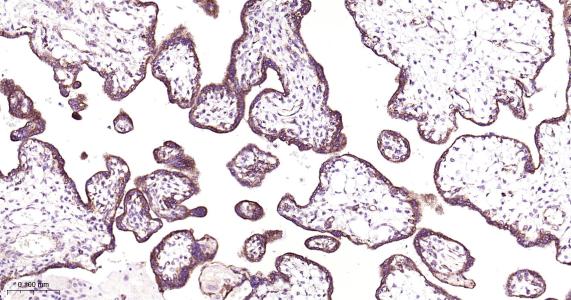

Paraformaldehyde-fixed, paraffin embedded Human Placenta; Antigen retrieval by boiling in sodium citrate buffer (pH6.0) for 15 min; Antibody incubation with HSD17B10 Monoclonal Antibody, Unconjugated(bsm-61523R) at 1:200 overnight at 4°C, followed by conjugation to the bs-0295G-HRP and DAB (C-0010) staining.